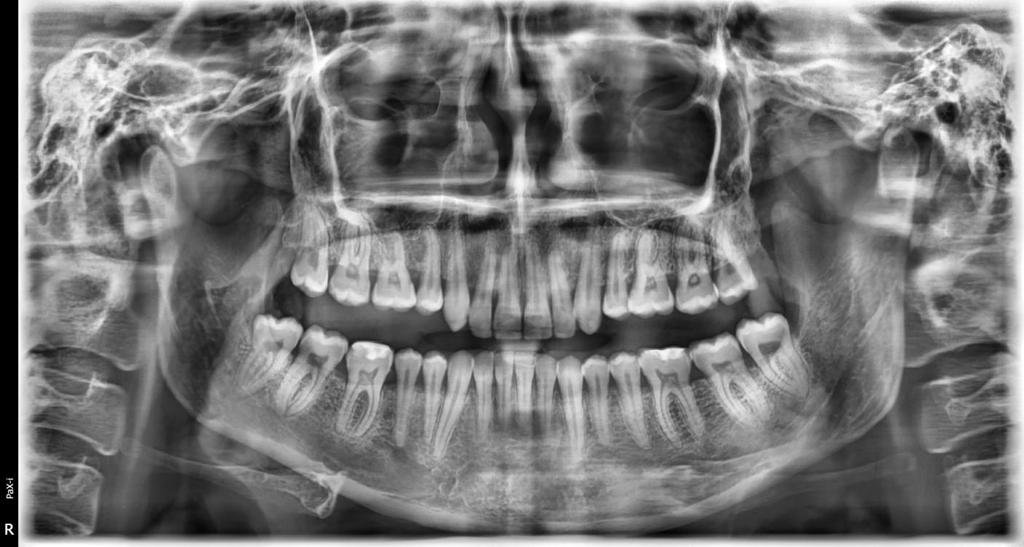

La radiografía panorámica es una prueba radiológica que sirve para recrear las estructuras óseas de la cara del paciente. De esta manera, el odontólogo obtiene una muestra en dos dimensiones del hueso maxilar superior, la mandíbula y los dientes y por consiguiente, puede determinar el estado de salud de aquellos aspectos que no es posible advertir en su habitual exploración visual.

Nos permiten el estudio de todas las estructuras de la cavidad bucal, con ellos podemos determinar el tipo de anomalía de forma de posición y de volumen de los dientes, además realizamos mediciones importantes para determinar el ancho de los maxilares, la relación entre ambos, así como la discrepancia hueso-diente, y una vez realizado todo este estudio en conjunto con los demás medios de diagnóstico, podemos concluir qué patología o mal oclusión presenta el paciente.

El estudio de ortodoncia es fundamental e imprescindible para empezar un tratamiento de ortodoncia, ya que, con él, tu Ortodoncista, va a obtener un diagnóstico completo sobre el que planificará el tratamiento adecuado. Es el elemento fundamental que marcará el éxito o fracaso del procedimiento, evitando imprevistos que retrasen o dificulten el proceso. El cual incluye: Radiografía panorámica, lateral de cráneo con cefalometrías, fotografías intraorales y modelos de estudio.